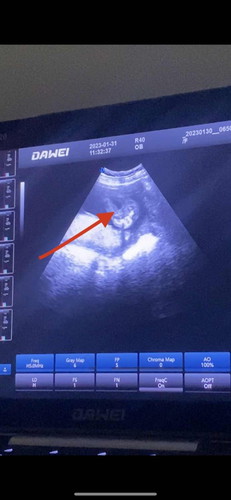

ลูกสาวไหมค่ะแบบนี้ จู๋จะโผล่ไหมค่ะ 😥😄 อิแม่ลุ้นจ้าา 18W 6 #ท้องแรกคะ #ขอคำแนะนำหน่อยค่ะ

น่าจะลูกสาวนะแม่ ไม่มีจู๋โผล่

สาวค่ะ ไม่มีจู๋